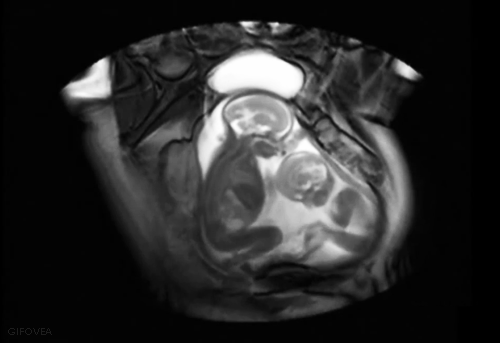

Twins interaction Uterus with MRI